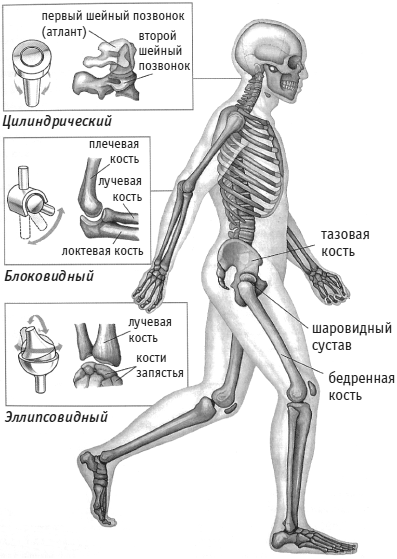

Диаграммы и схемы движения в суставах человека